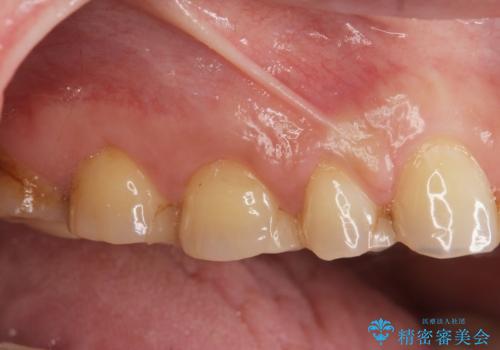

- 重度の歯ぎしり癖で歯がすり減り、見た目・噛み合わせの改善とこれ以上すり減る前の処置を希望され来院されました。

高さが短くなってしまった歯は、安定したクラウンを作るのが難しいため歯ぐきを下げる歯周外科を行ったのちに強度に優れるフルジルコニアクラウンで補綴治療を行います。